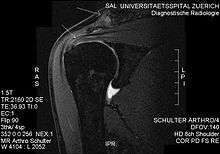

MRI showing subacromial impingement with partial rupture of the supraspinatus tendon. However, no retraction or fatty degeneration of the supraspinatus muscle.

Plain x-rays of the shoulder can be used to detect some joint pathology and variations in the bones, including acromioclavicular arthritis, variations in the acromion, and calcification. However, x-rays do not allow visualization of soft tissue and thus hold a low diagnostic value.[1] Ultrasonography, arthrography and MRI can be used to detect rotator cuff muscle pathology. MRI is the best imaging test prior to arthroscopic surgery.[1] Due to lack of understanding of the pathoaetiology, and lack of diagnostic accuracy in the assessment process by many physicians,[11] several opinions are recommended before intervention.